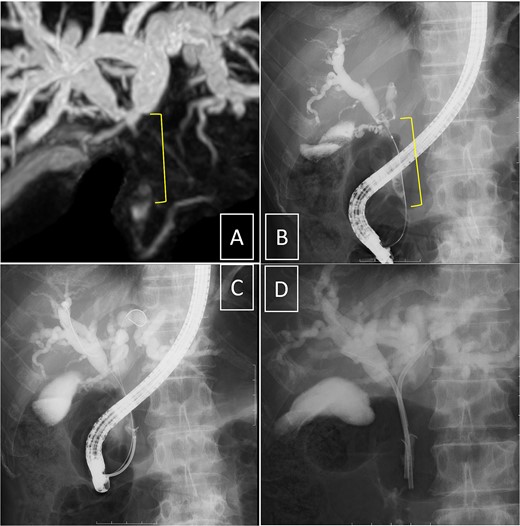

Endoscopic retrograde cholangiopancreatography (ERCP) was subsequently performed after the platelet count exceeded 50 × 109 /L (perioperative Day 27), and an endoscopic biliary stent (EBS) was inserted. Cholangiography with magnetic resonance imaging and ERCP revealed full circumferential stenosis in the mid-to-upper bile ducts without left and right bile duct disconnections (Fig. 4). Intraductal ultrasonography further demonstrated superficial tumor involvement of the perihilar bile duct, without extension to the left or right hepatic ducts. Histological examination confirmed adenocarcinoma, consistent with Bismuth type II pCCA [8]. Tumor resection was planned when the Prednisolone dose was reduced to 5 mg/day, and the platelet count remained >100 × 109 /L.

Cholangiography. Magnetic resonance imaging (A) and endoscopic retrograde cholangiopancreatography (B, D) reveal full circumferential stenosis in the mid-to-upper bile ducts without left and right bile disconnections. (C) The biopsy is conducted in the distal bile duct.